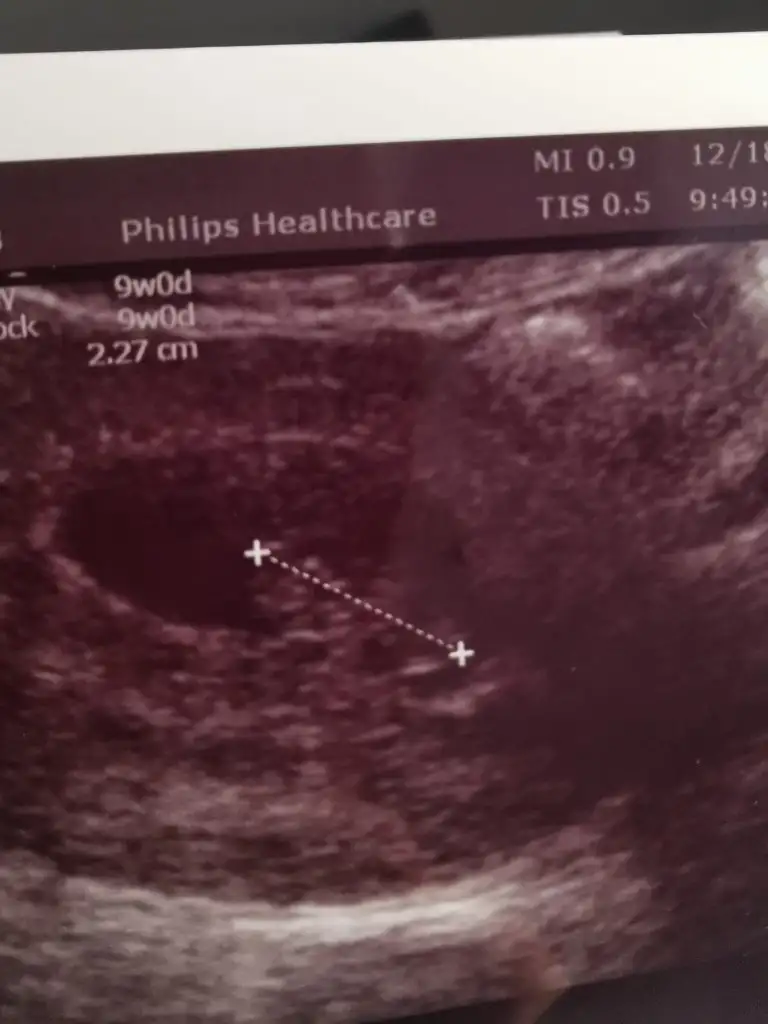

@ikrameyra merhabalar kız kardeşimin 9 haftalık bir tahminde bulunur musunuz. Şimdiden teşekkürler😊

IMG-20211222-WA0005.webp

• IMG-20211222-WA0003.webp

IMG-20211222-WA0003.webp

14,3 KB · Görüntüleme: 32

• IMG-20211222-WA0004.webp

IMG-20211222-WA0004.webp

17,2 KB · Görüntüleme: 40